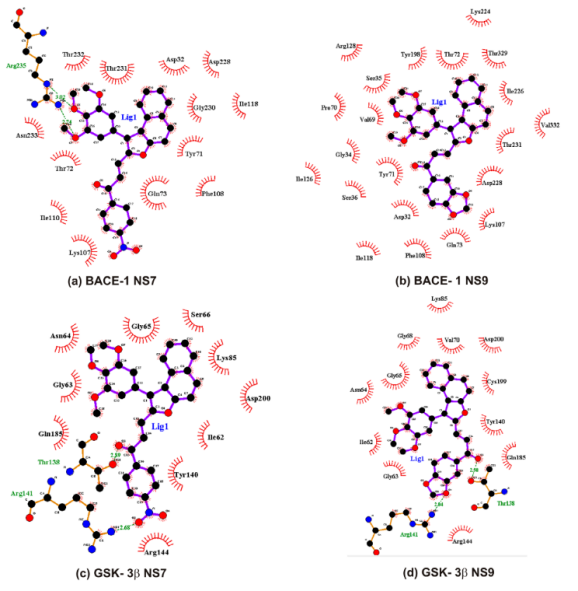

4.3.7 蛋白-小分子对接确定活性位点

4.3.11 刚性对接

3.3.2 刚性对接计算

在分子动力学模拟中,"刚性对接"通常指的是一种分子对接方法,其中配体和受体被视为刚性体,不考虑其内部的柔性。这种方法通常用于药物设计中,以快速评估药物分子与靶标蛋白的结合模式和亲和力。以下是一个使用AutoDock软件进行刚性对接的基本步骤:

准备配体和受体:首先,我们需要准备配体和受体的分子结构文件。这些文件通常可以从PDB(蛋白质数据库)下载,或者使用分子建模软件创建。在准备这些文件时,需要删除所有的水分子和其他不需要的小分子,并添加所有必要的氢原子。

选择和设置对接参数:在AutoDock中,我们需要设置对接参数,包括对接盒的大小和位置,以及搜索算法和评分函数。对接盒应该包含受体的所有潜在的结合位点。搜索算法(如遗传算法)用于寻找最优的配体-受体结合模式,评分函数用于评估每个模式的亲和力。

运行对接模拟:在设置好所有参数后,我们可以开始运行对接模拟。在这个过程中,AutoDock会寻找配体和受体之间的最优结合模式。

分析结果:模拟结束后,我们可以分析对接结果。AutoDock会输出一个包含所有可能结合模式的文件,我们需要选择一个或几个最优的模式进行进一步的分析。我们可以使用一些可视化软件,如PyMOL或Chimera,来查看和分析结合模式。

以上就是使用AutoDock进行刚性对接的基本步骤。这个过程需要足够的计算资源和时间,特别是对于大的或复杂的系统。此外,这个过程可能需要多次迭代和调整参数,以确保结果的准确性。

4.3.7 蛋白-小分子对接确定活性位点

在分子动力学模拟中,蛋白-小分子对接是一种常用的技术,用于预测小分子(例如药物分子)如何与蛋白质(例如酶或受体)相互作用。这种相互作用通常发生在蛋白质的活性位点,这是蛋白质上的一个区域,可以与小分子结合,从而影响蛋白质的功能。

对接过程通常涉及以下步骤:

首先,需要知道蛋白质的三维结构。这可以通过实验方法(如X射线晶体学或核磁共振)确定,或者使用计算方法预测。

然后,使用对接软件将小分子“对接”到蛋白质的可能的活性位点。这通常涉及计算不同的小分子姿态和位置,以及它们与蛋白质的相互作用能量。

对接结果通常会产生多个可能的小分子-蛋白质复合物。这些复合物然后可以根据他们的相互作用能量进行排名,以识别最可能的结合模式。

最后,可以使用分子动力学模拟来进一步研究小分子-蛋白质复合物的动态行为。这可以提供关于结合过程的详细信息,例如结合的稳定性,以及小分子和蛋白质之间的详细相互作用。

这些信息对于理解小分子如何影响蛋白质的功能,以及设计新的药物分子具有重要的价值。

4.3.11 刚性对接

在分子动力学模拟中,所谓的"刚性对接"(Rigid Docking)是一种假设参与对接的分子在对接过程中保持其原始的三维结构,即分子的所有原子的相对位置保持不变。这种方法通常用于对接过程的初步筛选阶段,因为它的计算成本相对较低。

刚性对接通常涉及将一个分子(通常是小分子或药物分子)在另一个分子(通常是大分子,如蛋白质)的表面上进行旋转和平移,以找到最佳的结合位点和姿态。在这个过程中,被认为是"刚性"的分子不会发生形状和构象的变化。

然而,刚性对接的一个主要限制是它忽略了分子在结合过程中可能发生的构象改变。在现实中,分子通常会在结合过程中发生某种程度的构象变化,以适应对方的结构。因此,尽管刚性对接在初步筛选阶段可能非常有用,但在需要更精确的预测时,可能需要考虑到分子的柔性,这就涉及到"柔性对接"或"半柔性对接"的方法。